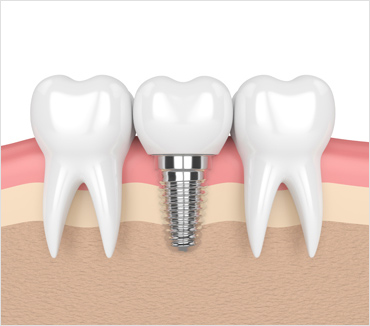

Structure of dental implants

Dental implants are a great option for replacement of a missing tooth or teeth. Most dental implants contain a metal body inserted into the jawbone, an attachment referred to as an abutment, and a crown that serves as the artificial replacement tooth. Dental implants become fused to your jawbone through a process called osseointegration, which allows for normal chewing, speech, and function just like a natural tooth.